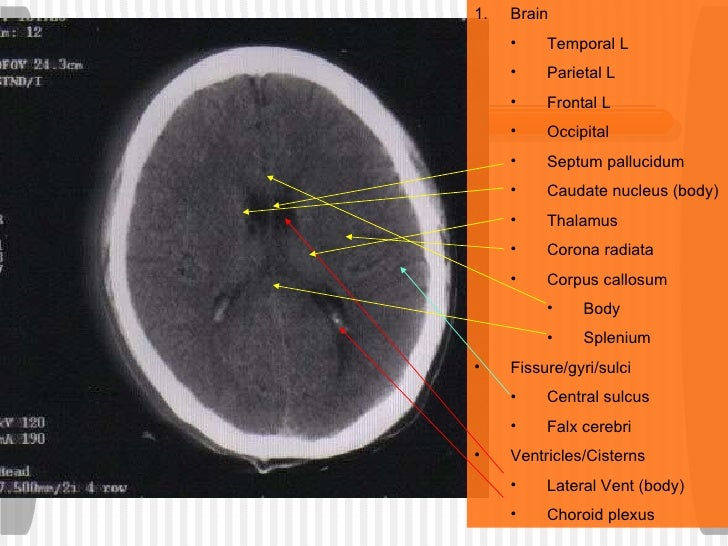

The fibers of the internal capsule radiate widely as they pass to and from the various parts of the cerebral cortex, forming the corona radiata and intermingling with the fibers of the corpus callosum. corona radiata. projection axons in forebrain *sensory axons from thalamus to sensory cortices *motor axons from motor cortices to brainstem and -between lenticular nucleus and head of caudate nucleus -contains thalamic radiations (cortical connections) with frontal lobe and PFC and frontopontine fibers.

15 + Frontal Corona Radiata Function HD WallpapersDissection showing the course of the cerebrospinal fibers. In neuroanatomy, the corona radiata is a white matter sheet that continues ventrally as the internal capsule and dorsally as the centrum semiovale. The centrum semiovale and posterior PVWM contain the corona radiata, which includes fibers originating in the motor cortex that continue ventrally to.